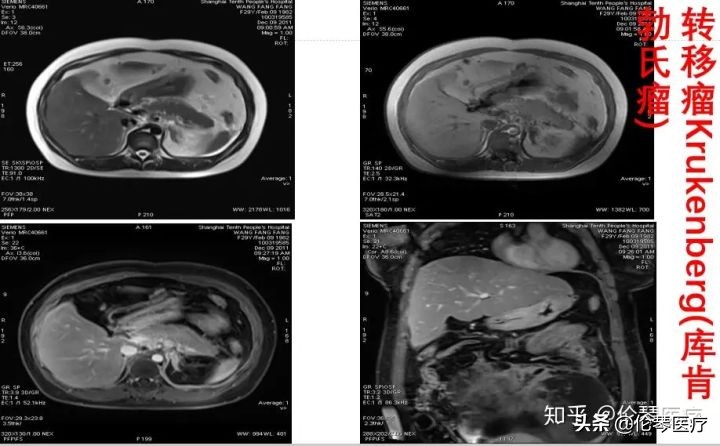

如图所示病例,初步诊断是常见的卵巢上皮癌,后来通过磁共振的多方位成像,发现肿瘤在腹腔里有几个组成部分,且发现上腹部的胃也有问题。最后,我们术前诊断是胃癌到卵巢的转移,称为库肯勃氏瘤。